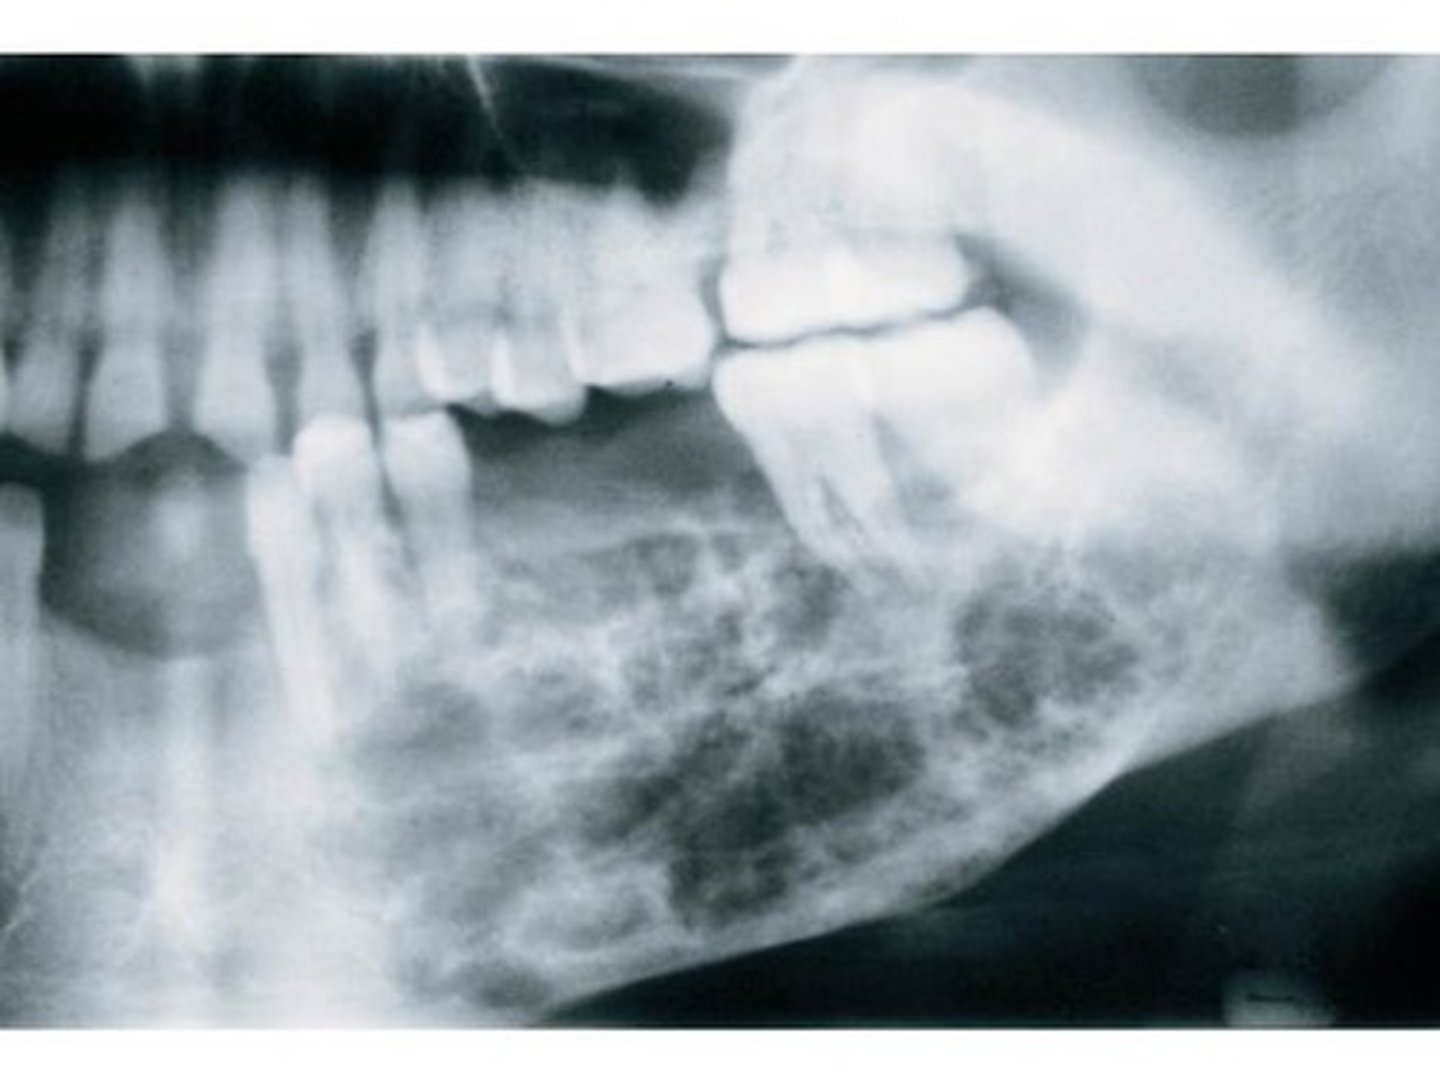

Radiographic Signs of Odontogenic Myxoma

variable

multilocular

soapbubble

honeycomb

straight thin septa